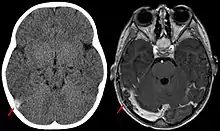

![]() Trombosis del seno venoso cerebral vista mediante resonancia magnética | ||

La trombosis del seno venoso cerebral (CVST) es la presencia de trombosis (coágulo sanguíneo) en el seno venoso dural, que recibe sangre de venas externas e internas del cerebro. Los síntomas de esta enfermedad pueden incluir dolor de cabeza, visión anormal, cualquiera de los síntomas de un accidente cerebrovascular (debilitamiento de los músculos de la cara y extremidades de una mitad del cuerpo) e infartos. El diagnóstico se realiza normalmente por tomografía axial computarizada (CT/CAT scan) o resonancia magnética (MRI) empleando el contraste radiológico para demostrar obstrucción de los senos venosos por trombos.[1]

Hay varias formas de neuroescaneo que pueden determinar la presencia de la trombosis del seno venoso cerebral. Los edemas cerebrales e infartos venosos pueden hacerse visibles en cualquier modalidad, pero para la detección del trombo sí, el tipo de escaneo más usado comúnmente son la tomografía axial computarizada (CT) y la resonancia magnética (MRI). Ambas usan varios medios de radiocontraste para elaborar un venograma y visualizar las venas en torno al cerebro.[1]

La tomografía axial computarizada tiene una capacidad de detección que para algunos expertos supera la de la resonancia magnética. Esta prueba se basa en la inserción, a través de una inyección en la vena (normalmente en el brazo), de una sustancia radiopaca. Tras un tiempo, el que tarda el torrente sanguíneo en llevar la sustancia al cerebro, el escaneo se realiza. La sensibilidad de este test es de 75-100% (detecta de 75 a 100% de todos los coágulos presentes), y una especificidad de 81-100% (sería incorrectamente positivo en un 0-19%).[6]

La resonancia magnética venosa emplea los mismos principios, pero la modalidad de escaneo usada es la resonancia magnética. La MRI tiene la ventaja de ser mejor a la hora de detectar peligro para el cerebro como resultado del incremento de la presión en las venas obstruidas. No obstante, este mecanismo no se encuentra disponible en muchos hospitales y su interpretación puede resultar dificultosa.[6]